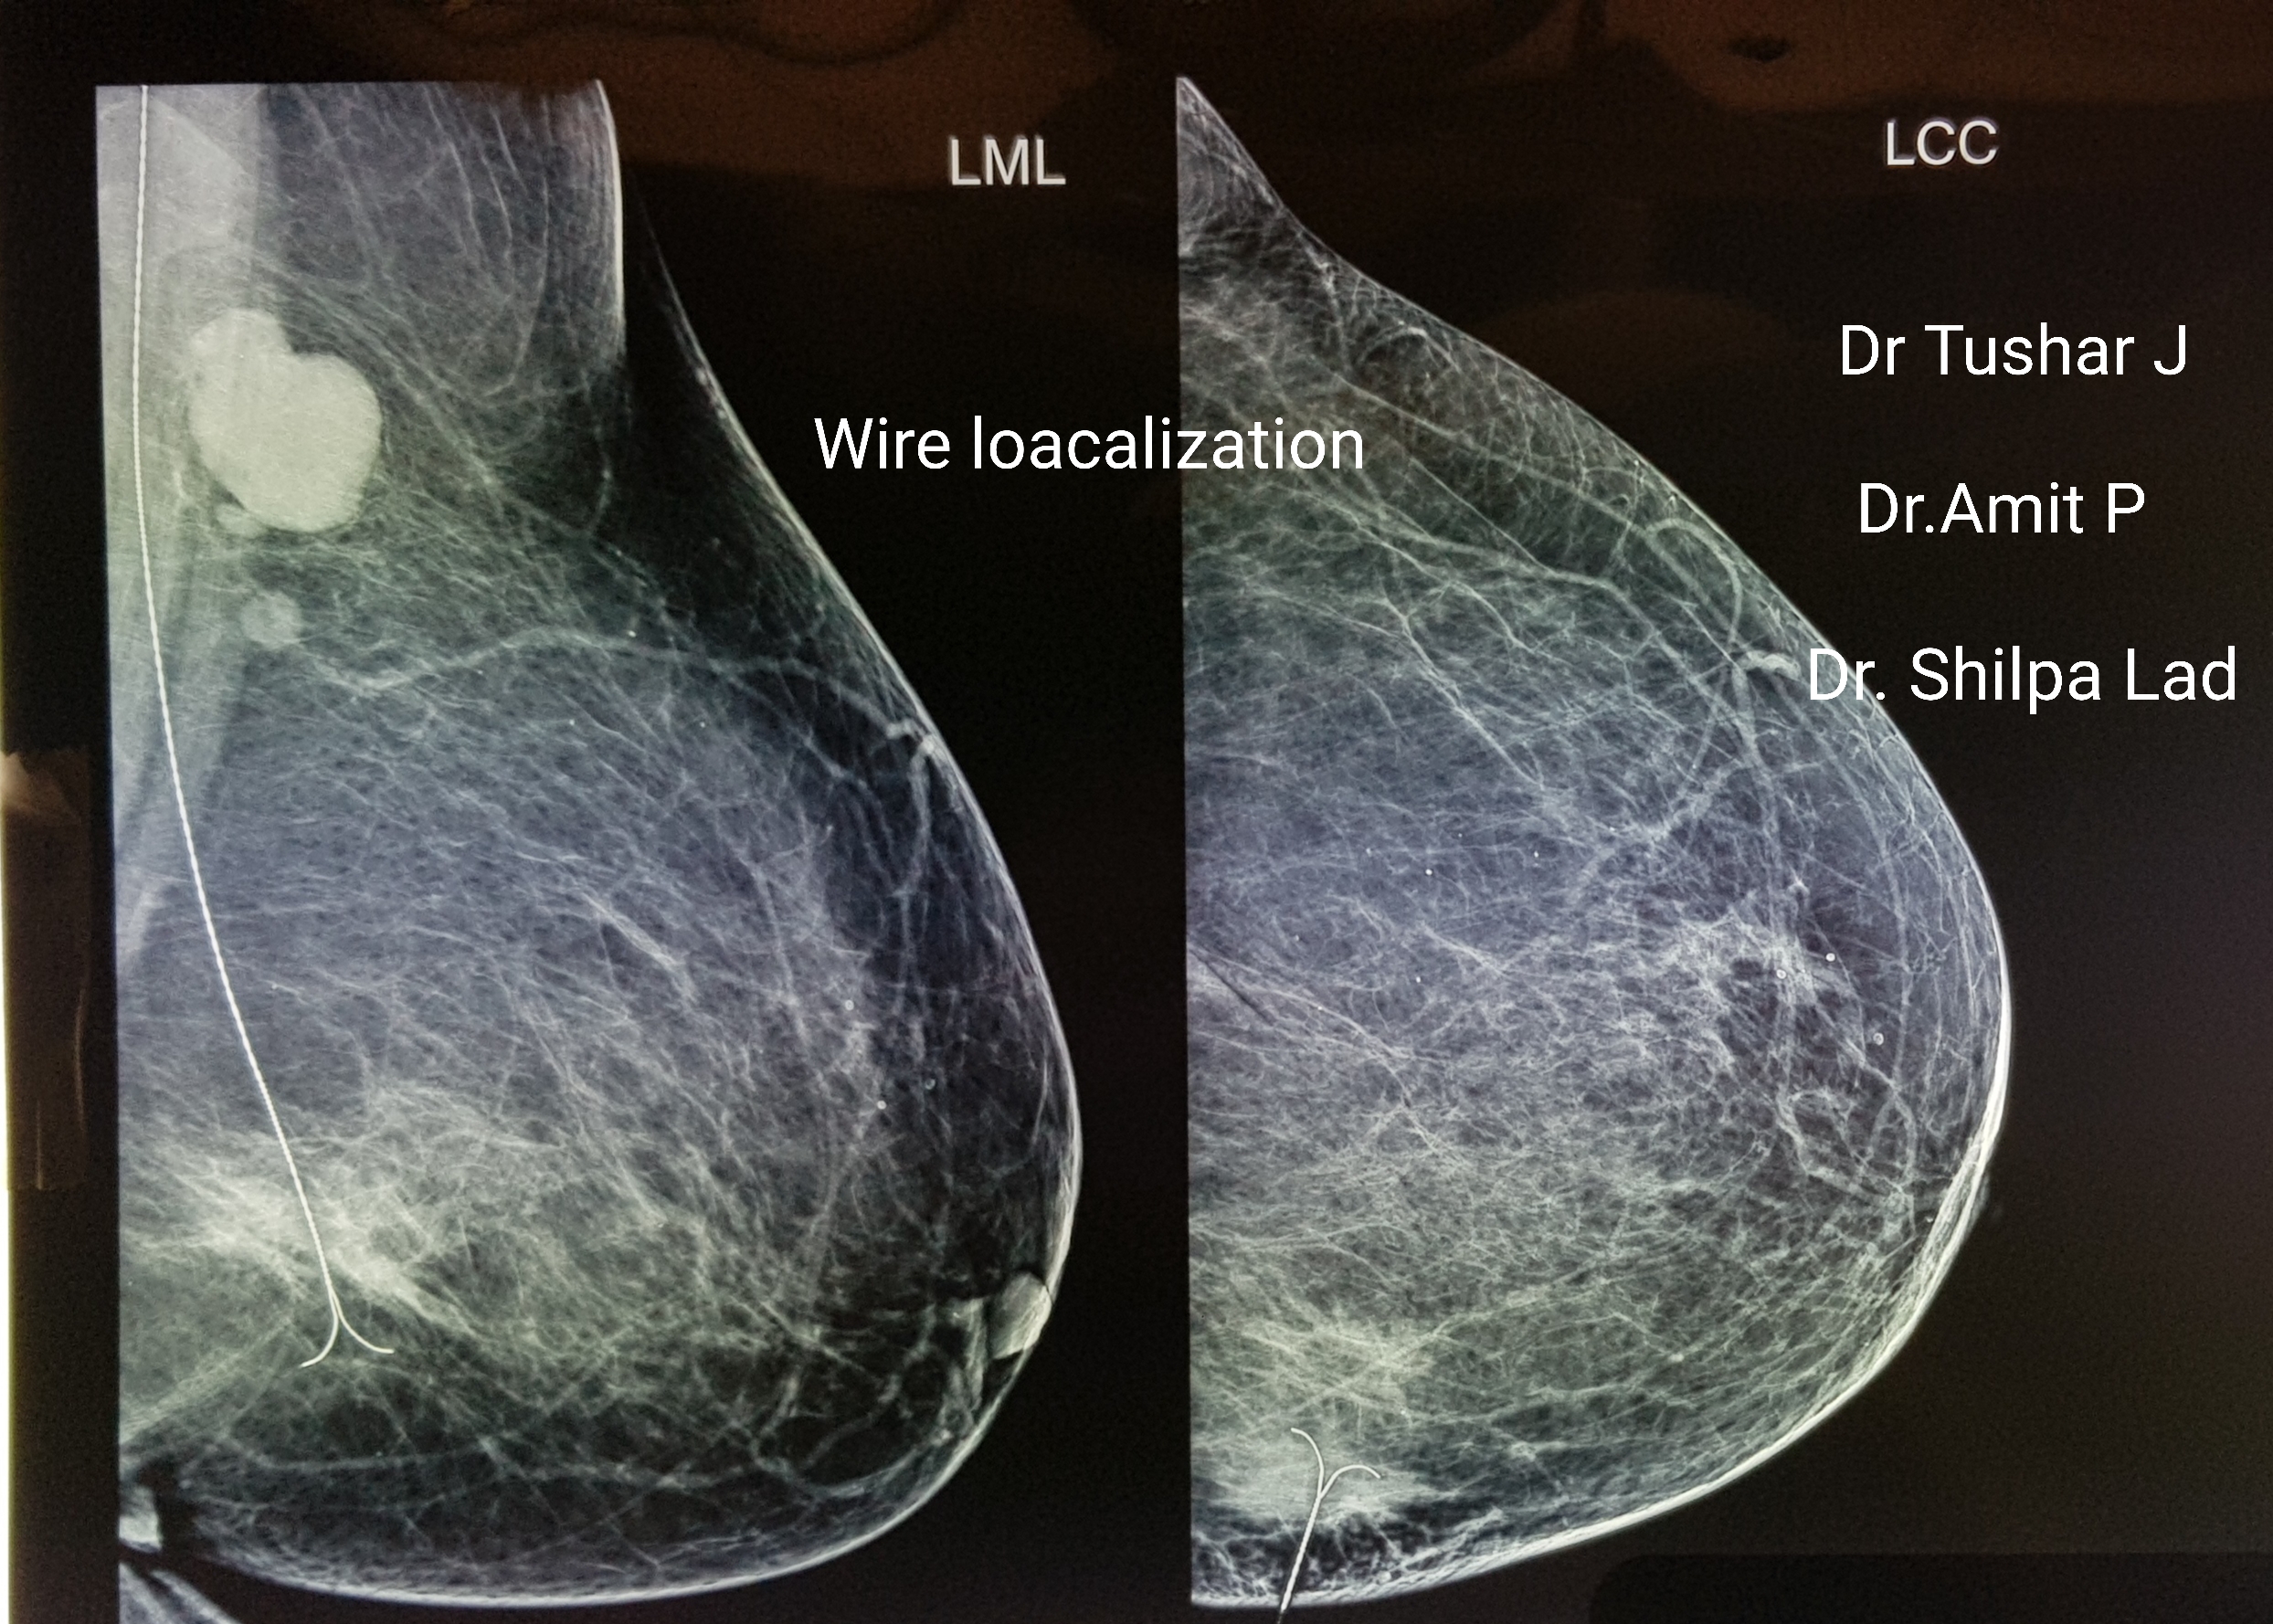

Reduction Oncomammoplasty